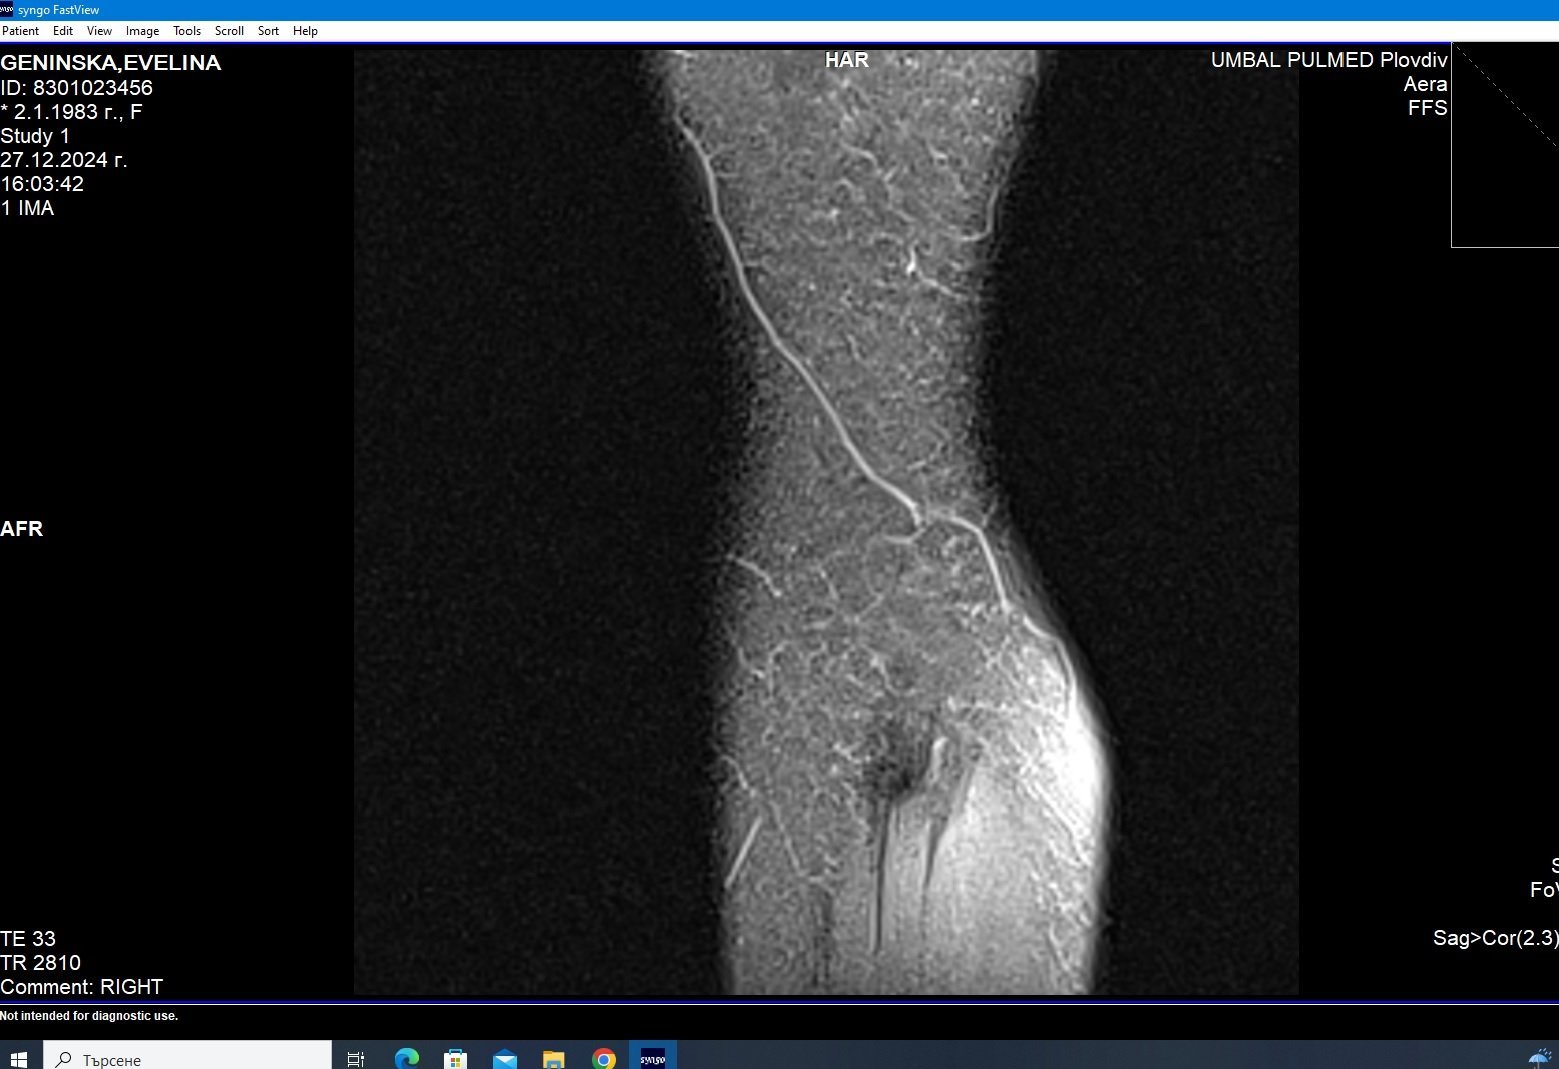

Здравейте, тъй като незнам как да ви кача целия диск Ви качвам малко снимки

Здравейте, благодаря за ЯМР-а.

Подборът на срезове/снимки не е най- добрият. Моля да изпратите диска на имейл: infо@beta-clinic.com или чрез спедитор на адреса на Бета клиник.